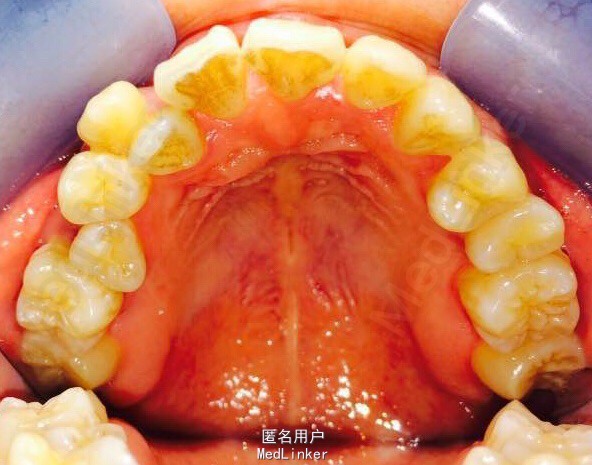

女,23岁,重度侵袭性牙周病,有家族遗传性

讨论: 牙周治疗处于维护稳定阶段,下合2—2牙槽骨吸收至根尖1/3水平,是否适合正畸? 下合前牙的保留问题?